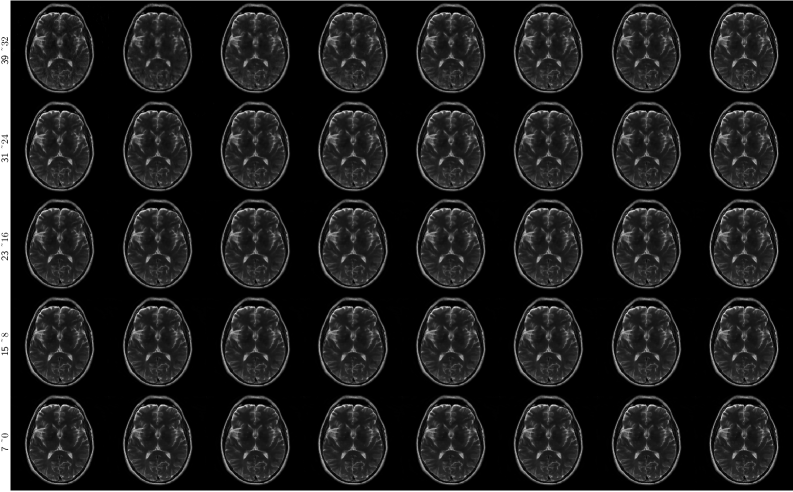

Appendix D Evolution of the reconstruction process

Refer to caption

Figure 8: The evolution of reconstruction 𝐱ttrue\mathbf{x}_{t}^{\text{true}} over noise timestep from 39 to 0.